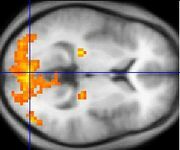

A fMRI scan showing regions of activation in orange, including the primary visual cortex (V1, BA17).

Functional MRI (fMRI) measures signal changes in the brain that are due to changing neural activity. The brain is scanned at low resolution but at a rapid rate (typically once every 2-3 seconds). Increases in neural activity cause changes in the MR signal via T2* changes[19]; this mechanism is referred to as the BOLD (blood-oxygen-level dependent) effect. Increased neural activity causes an increased demand for oxygen, and the vascular system actually overcompensates for this, increasing the amount of oxygenated hemoglobin (haemoglobin) relative to deoxygenated hemoglobin. Because deoxygenated hemoglobin attenuates the MR signal, the vascular response leads to a signal increase that is related to the neural activity. The precise nature of the relationship between neural activity and the BOLD signal is a subject of current research. The BOLD effect also allows for the generation of high resolution 3D maps of the venous vasculature within neural tissue.